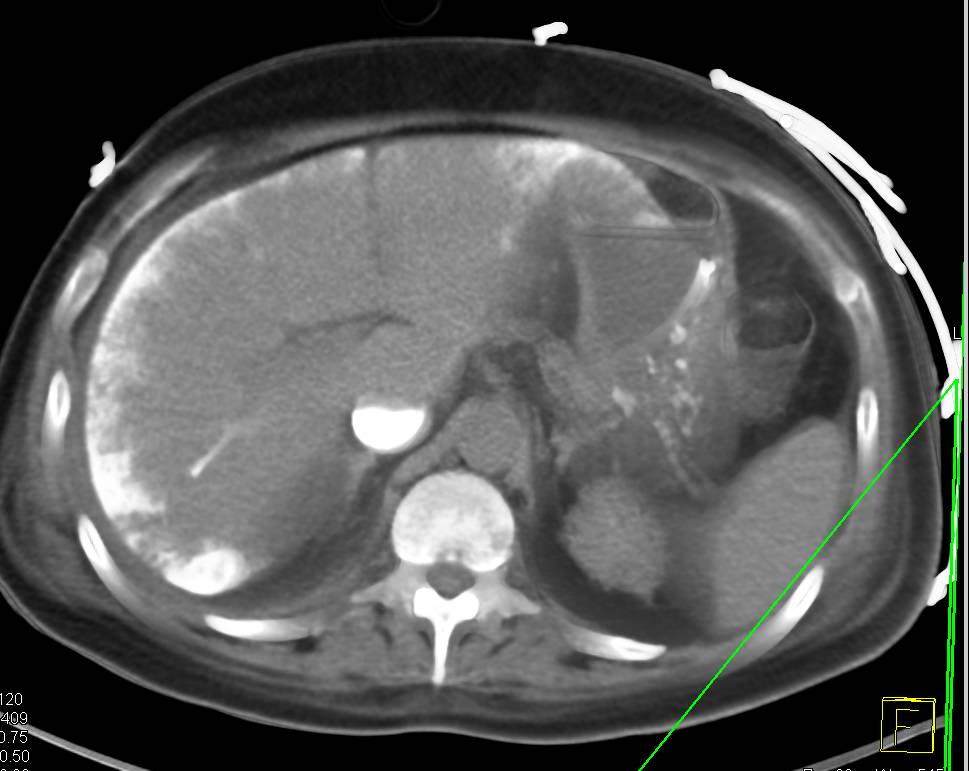

Recurrent Hepatocellular Carcinoma (Hepatoma) with CTA